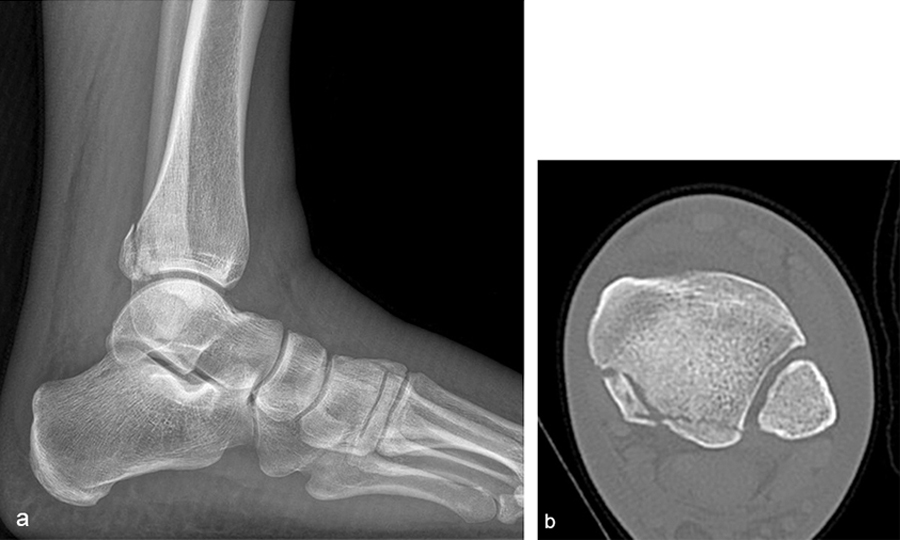

A 27-year-old man fell from a ladder sustaining a proximal fibula fracture (Fig 1) with a multipart posterior malleolar fracture (Fig 2). The patient was treated operatively with direct reduction and plate fixation of the posterior malleolar components. Intraoperative testing demonstrated continued syndesmotic instability requiring fixation (Fig 3). The syndesmosis was reduced in direct fashion and stabilized with a provisional K-wire and clamp before insertion of a FIBULINK Implant (Fig 4).

A 34-year-old woman was injured while riding a motor scooter sustaining an ankle fracture with associated syndesmotic injury (Fig 6a). The fibula was reduced anatomically and stabilized with a 1/3 tubular plate (Fig 6b). The unstable syndesmosis was reduced and provisionally stabilized with a K-wire and clamp (Fig 7) before FIBULINK Implant System implantation (Fig 8). The patient had an uneventful recovery (Fig 9).